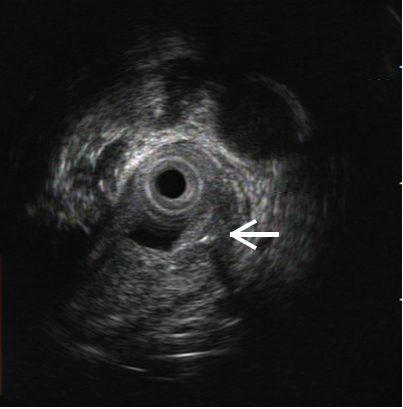

相對(duì)于食管腔而言,魚(yú)刺太細(xì),且可能不斷移動(dòng)。盡管有CT圖像輔助,但仍無(wú)法直接幫助內(nèi)鏡定位,用內(nèi)鏡在黏膜下層尋找,無(wú)異于大海撈針。為此,耳鼻喉科、麻醉科、超聲科、影像科和消化內(nèi)鏡中心的專家們組織了多學(xué)科討論,決定采用氣管插管麻醉,以內(nèi)鏡隧道技術(shù)聯(lián)合術(shù)中超聲內(nèi)鏡進(jìn)行食管黏膜下切開(kāi)探查。由于需要?jiǎng)佑枚喾N內(nèi)鏡設(shè)備,搬動(dòng)到大手術(shù)室十分不便,麻醉科決定為內(nèi)鏡中心提供麻醉設(shè)備支持,在內(nèi)鏡中心完成氣管插管,為手術(shù)提供更便利的條件。

但手術(shù)遠(yuǎn)比想像中更為困難,由于解剖結(jié)構(gòu)的因素,內(nèi)鏡在高位食管建立黏膜下隧道本來(lái)就有很高難度,還要在狹窄的隧道內(nèi)完成超聲內(nèi)鏡檢查,既不能發(fā)生食管穿孔,又要準(zhǔn)確定位魚(yú)刺,挑戰(zhàn)十分嚴(yán)峻。內(nèi)鏡中心多位醫(yī)生輪番上陣,在護(hù)理團(tuán)隊(duì)嫻熟配合下,經(jīng)過(guò)長(zhǎng)達(dá)數(shù)小時(shí)的地毯式搜尋,終于發(fā)現(xiàn)魚(yú)刺的蹤跡。鑒于已發(fā)生過(guò)取出過(guò)程夾斷魚(yú)刺的情況,為保證魚(yú)刺完整,在反復(fù)超聲探查判斷術(shù)中引發(fā)魚(yú)刺穿破食管的可能性不大后,醫(yī)生們采用了一種新辦法:在魚(yú)刺遠(yuǎn)端的食管黏膜再切開(kāi)一道深度接近肌層的小切口,然后自魚(yú)刺近端建好的黏膜下隧道再次進(jìn)鏡,終于將這根長(zhǎng)約2.4cm的“流浪”魚(yú)刺完整地從遠(yuǎn)端的切口里“推趕”了出去。